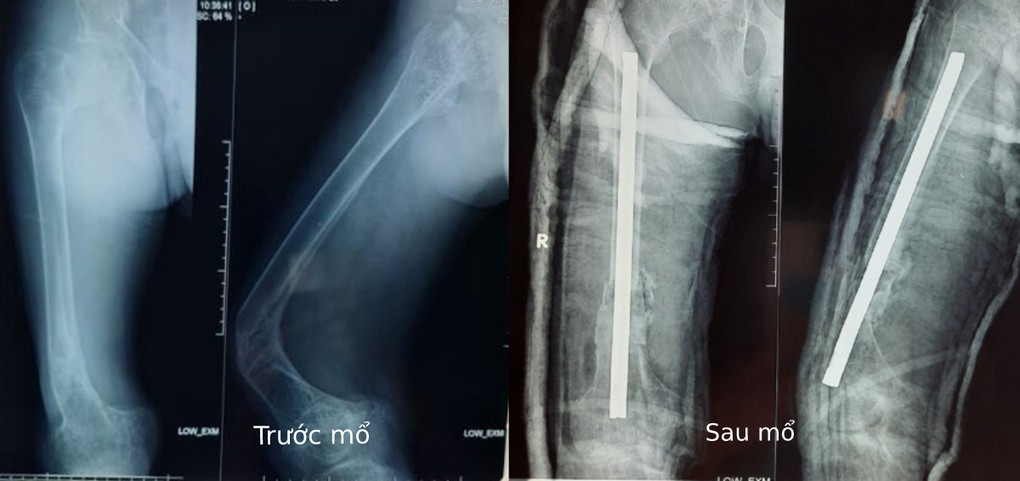

Bác sĩ chuyên khoa II Phan Văn Tiếp, khoa Chấn thương chỉnh hình, Bệnh viện đa khoa Xuyên Á, cho biết người bệnh vào cấp cứu ngày 10/10 trong tình trạng đùi phải gãy xương và biến dạng, đau đớn, không thể đi lại.

Bác sĩ Tiếp cho biết ca phẫu thuật cho bệnh nhân khá phức tạp vì xương đã gãy nhiều lần, lại rất mềm, cần thao tác nhẹ nhàng để các phần xương khác không vỡ vụn. Ê kip phẫu thuật đã cắt từng đoạn xương cong, biến dạng, khoan rộng ống tủy, xoay xếp ngược các xương sao cho thẳng trục rồi cố định bằng đinh Kuntscher. Bệnh nhân được ghép xương tự thân và khâu da từng lớp, sau cùng là nẹp bột đùi chân phải.

Hiện, 6 ngày sau mổ, sức khỏe người bệnh tương đối ổn định, vết thương đang phục hồi tốt. Anh sẽ tập vật lý trị liệu để đi lại và sinh hoạt bình thường.